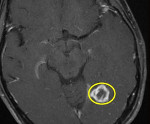

• Казеозная. Состоит из центрально расположенного очага творожистого некроза, окружённого плотной гранулематозной тканью. При томографии даёт гипо- и изоинтенсивный сигнал в обоих режимах. Контрастирование сопровождается кольцевидным усилением изображения.

• МРТ головного мозга. Рекомендовано тщательное комплексное исследование с использованием Т1/Т2 режимов, диффузионно-взвешенных изображений, МР-спектроскопии. В пользу туберкуломы говорит небольшой перифокальный отёк, наличие оболочки, кольцевидное контрастирование.